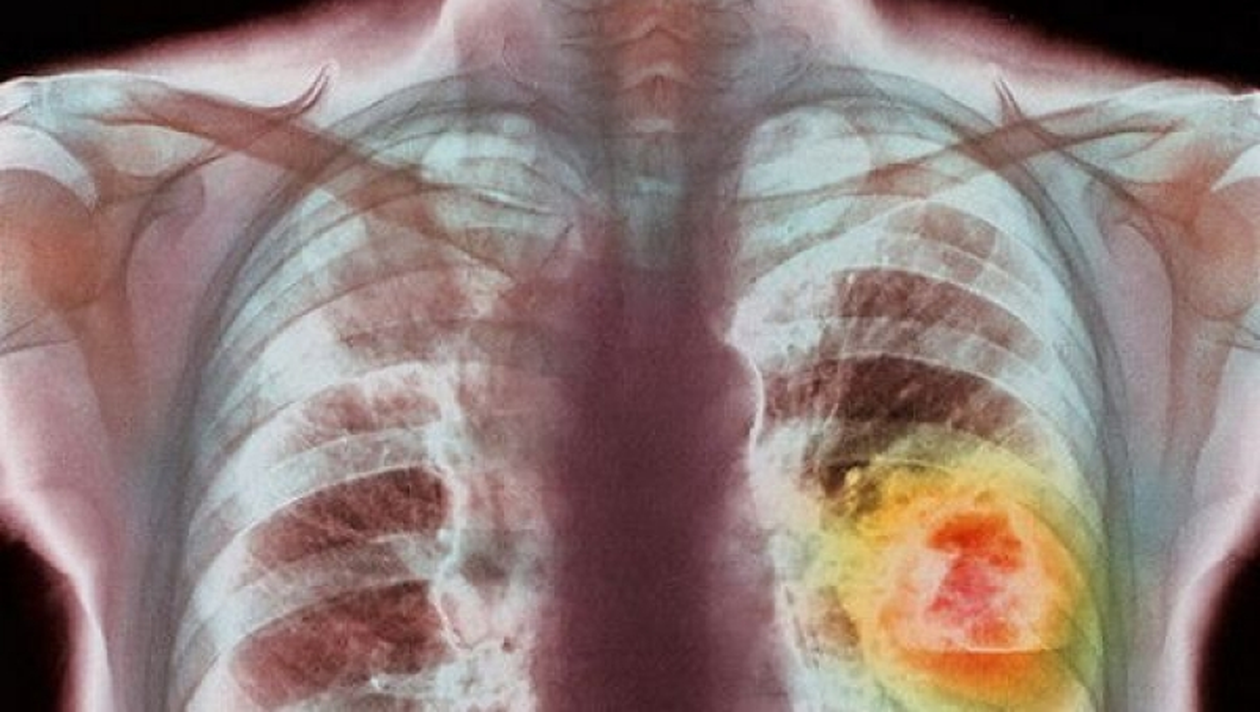

Un aparat de ultimă generație care ajută la depistarea precoce a trei tipuri de cancer, prin analize medicale, a fost cumpărat de o asociație din Prahova, județ cu 10.000 pacienți oncologici înregistrați. Este primul astfel de aparat din România care se folosește strict pentru pacienți.

Aparatul este, de asemenea, singurul care lucrează în afară de biopsie solidă și biopsie lichidă. Are capacitatea de a determina din sânge modificările ADN-ului mutant pentru 3 tipuri de cancer: colorectal, pulmonar si de piele. În Prahova sunt 10.000 pacienți oncologici înregistrați.